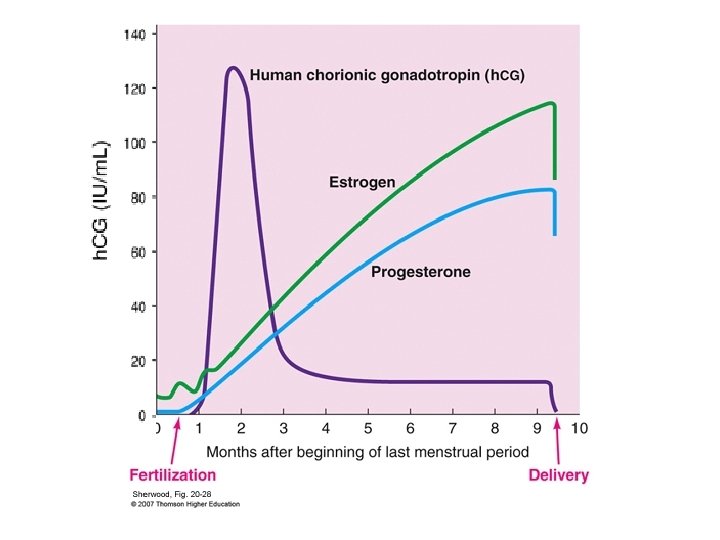

TVS “Milestones” Versus βh. CG m. IU/m. L Weeks Detection Level >5 3 -4 Choriodecidual thickening 100 Gestational sac (D Zone) 1000 -1500 Yolk sac Heart motion 7000 4 4 -5 5 - 6 10, 000 6 Embryonic Movem. > 10. 000 6 - 7 Maximum level 50, 000 to 100, 000 8 -10

The Post-evacuation Surveillance. How? A baseline serum β -h. CG level is obtained within 48 hours after evacuation. Levels are monitored every 1 to 2 weeks while still elevated to detect persistent trophoblastic disease (GTN). These levels should progressively fall to an undetectable level (<5 mu/ml). If symptoms are persistent, more frequent β h. CG estimation and U/S examination ± D&C are advised RCOG Guideline No. 38 ; 2010

Cunningham et al, Williams Obstetrics, 23 ed , 2010

At the 9 week follow up the β h. CG level : 2 u/L Is this level sufficient to stop follow up ? No 4 - The Scenario case Cunningham et al, Williams Obstetrics, 23 ed , 2010

What Is The Optimum Follow-up Period After Which Pregnancy Is Allowed? It depends upon when h. CG has reverted to normal Ø ≤ 56 days of the pregnancy event: Follow up is 6 months from the date of uterine evacuation. Ø >56 days of the pregnancy event : Follow up is 6 months from normalization of the h. CG level. RCOG Guideline No. 38 ; 2010 At this period levels of βh. CG are monitored every month Practically once βh. CG has normalized after molar evacuation, the possibility of GTN developing is very low.